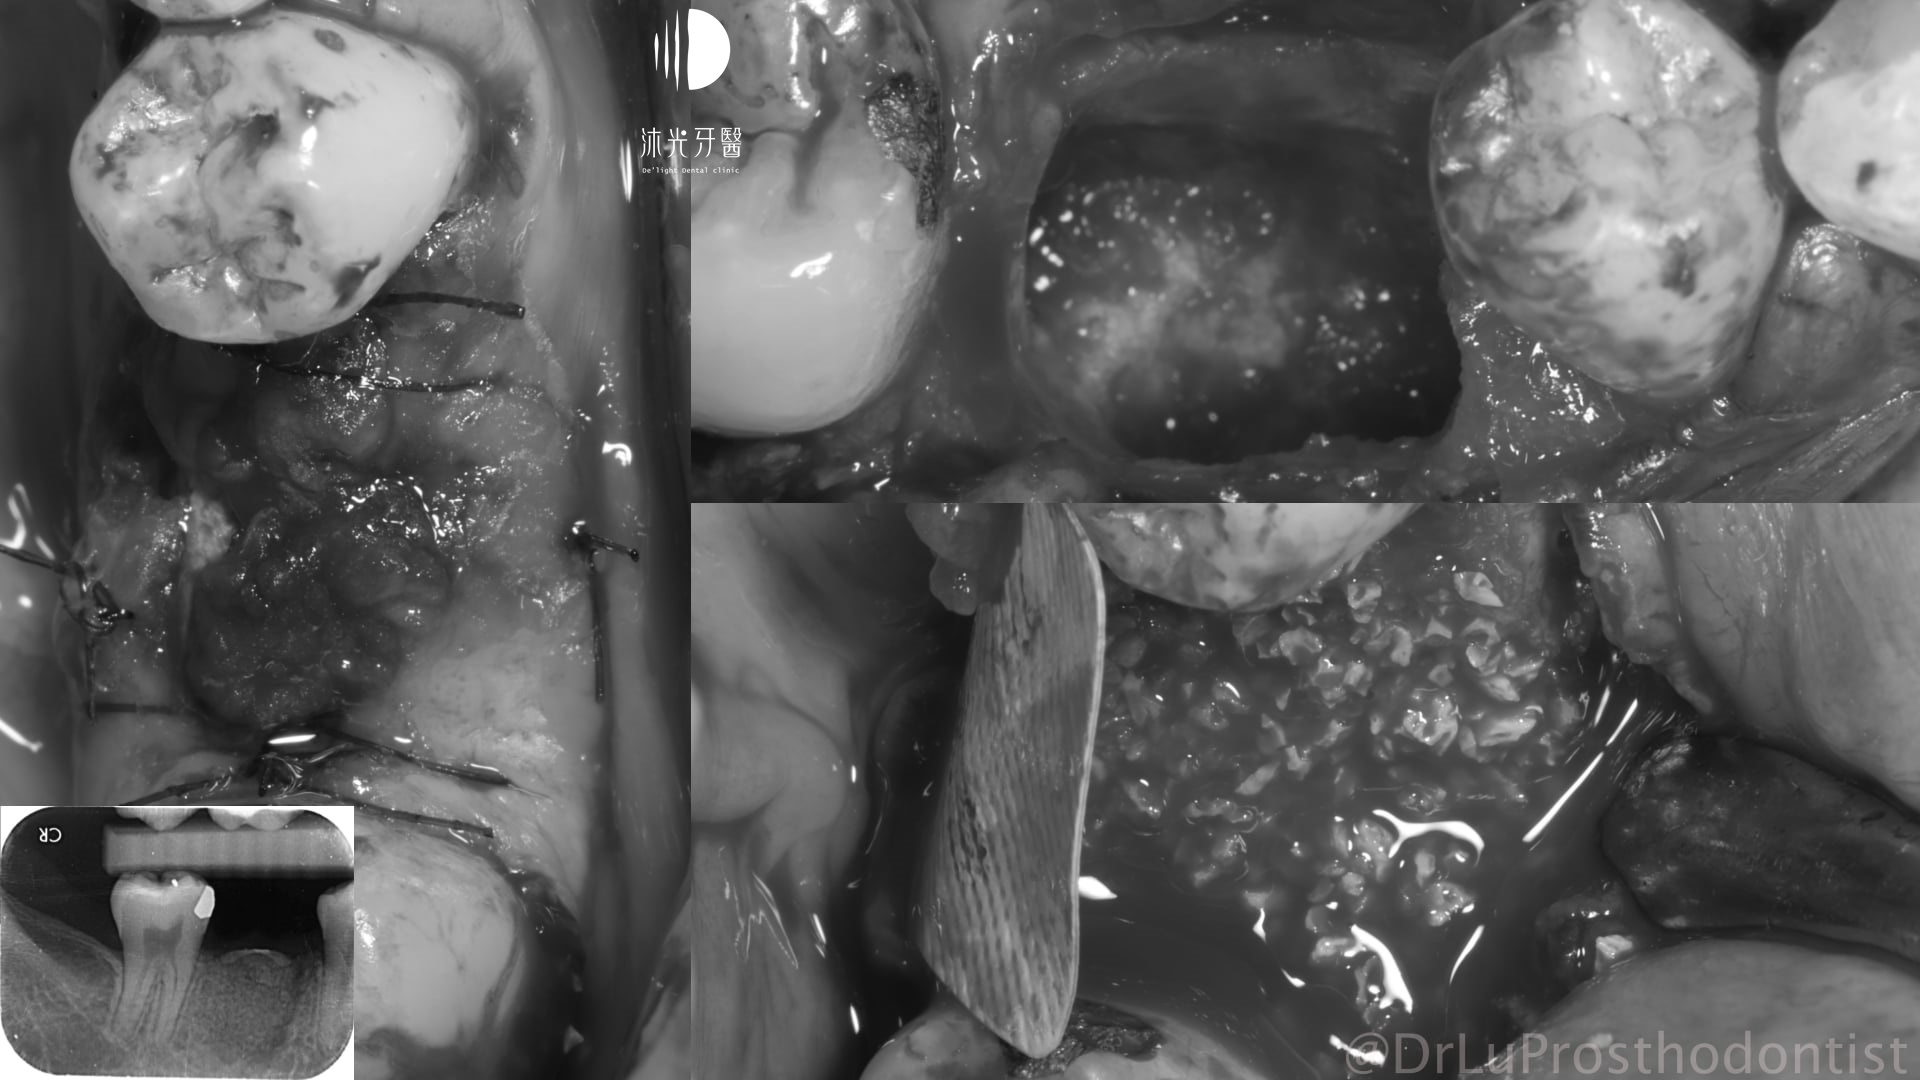

X光及口內檢查可知齒槽骨長期發炎感染後嚴重吸收,拔牙當下整個拔牙窩就像一個大窟窿,裡面滿是感染形成的肉芽組織。整個植牙重建過程也沒辦法像一般患者這麼輕鬆(戲稱植牙重建的吃全餐),從拔牙清創補骨、植牙、補牙齦將缺失的組織一一重建好,才能完成接近自然牙狀態的植牙贋復。